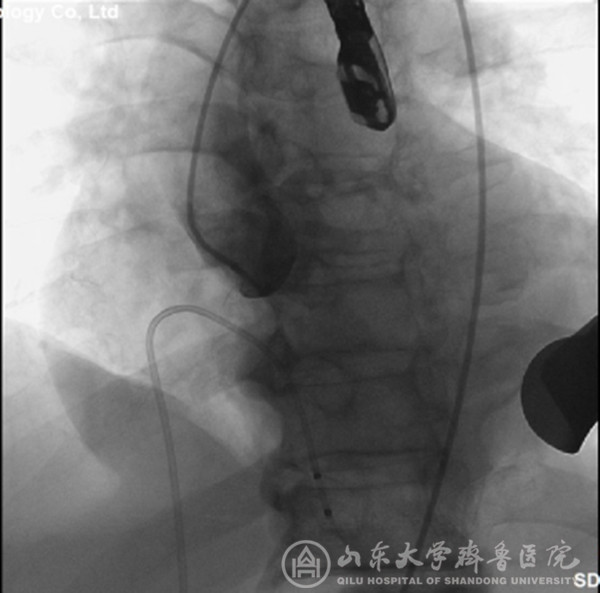

经过充分细致地准备,TAVI团队在复合手术室实施手术。根据患者的病情特点,术中做好各种应急预案,备好体外循环,维持血流动力学平稳。根据术前CT分析和术中主动脉根部造影情况(图1),选择最佳投照体位。选用29mm的介入主动脉瓣膜,经心尖途径,依次定位、顺序释放介入瓣膜(图2),造影及心脏超声检查示:人工瓣膜启闭功能正常,主动脉瓣无返流,未见明显瓣周分流(图3)。因患者心功能极差,手术操作过程中,多次出现频发及多源性室早、血压下降等情况,TAVI团队(心外科、心内科、麻醉科、手术室、心脏超声室等)医护人员齐心协力、整体配合,精心操作,积极对症处理,用时近2小时顺利完成手术。患者术后出现左心衰、血压低、尿量少等情况,给予积极处理,病情逐渐稳定。术后第2天拔气管插管,术后第5天转出监护病房。术后第7天,可下床活动,无心慌、胸闷等症状。术后第12天,病情稳定,治愈出院。术后2个月随访,患者基本日常活动不受影响,饮食正常,无心衰症状,恢复效果满意。

图1 主动根部造影,可见主动脉瓣大量返流